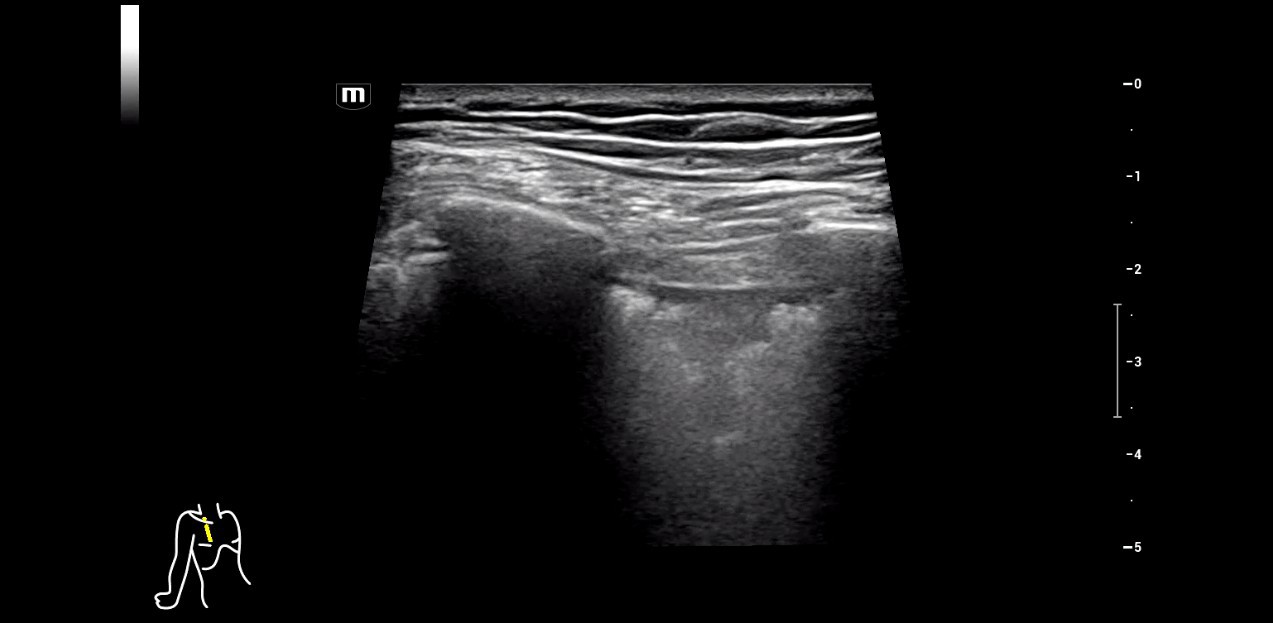

When working in an intensive care unit, obtaining a quick overview of a patient's health status is crucial. Sonography can non-invasively image multiple entities, some of which may be critical, in real-time. However, using this technology requires equipment that offers high flexibility without compromising image quality. For his department, specialized intensive care physician Dr. Armin Seibel relies on the high-end color Doppler ultrasound device Resona I9 from Mindray, which offers exceptional image quality, multifunctionality, and a long battery life.

Diverse application possibilities

Dr. Seibel chose Resona I9 for various reasons. First, the high-end device offers excellent image quality with high resolution, as well as focused examination techniques that facilitate diagnosis. For instance, he frequently uses contrast-enhanced ultrasound (CEUS) to clarify uncertain findings.